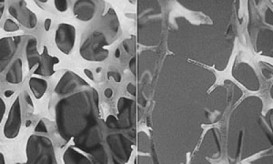

Ιδιαίτερα ακριβή αποδεικνύεται για το σύστημα υγείας η διαχείριση της οστεοπόρωσης και κυρίως των καταγμάτων που οφείλονται σε αυτή,...